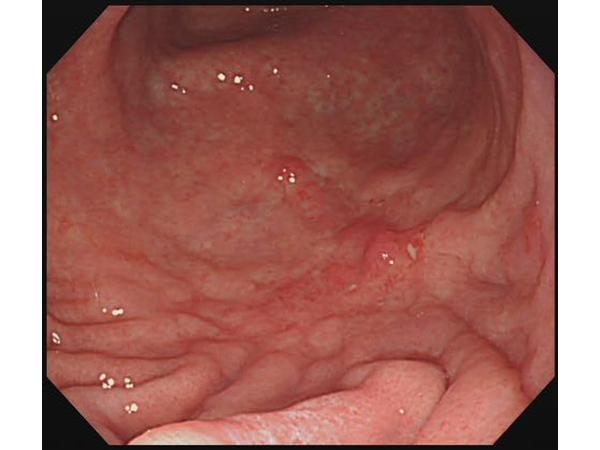

検診で発見した症例

無症状の早期発見の胃がんです。特殊な色素散布(インジゴ散布)により、がんが明瞭になります。